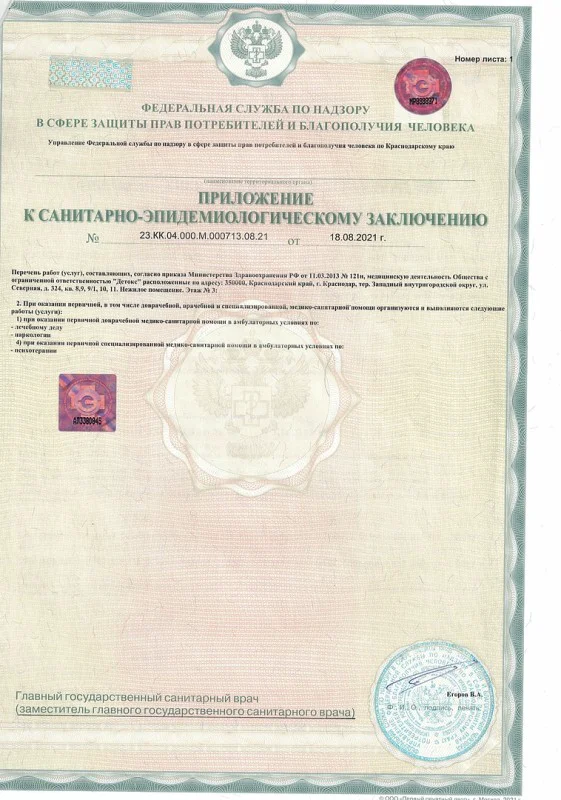

Лицензия на осуществление медицинской деятельности

Лицензия на осуществление медицинской деятельности

Лицензия на осуществление медицинской деятельности

Лицензия на осуществление медицинской деятельности

Лицензия на осуществление медицинской деятельности

Лицензия на осуществление медицинской деятельности

Лицензия на осуществление медицинской деятельности

Лицензия на осуществление медицинской деятельности